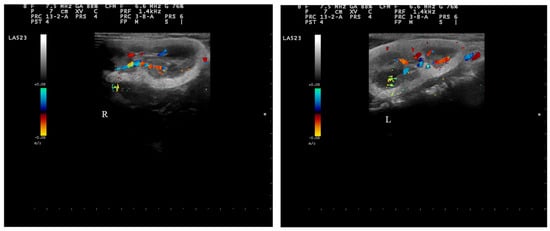

2.4. Doppler Examination